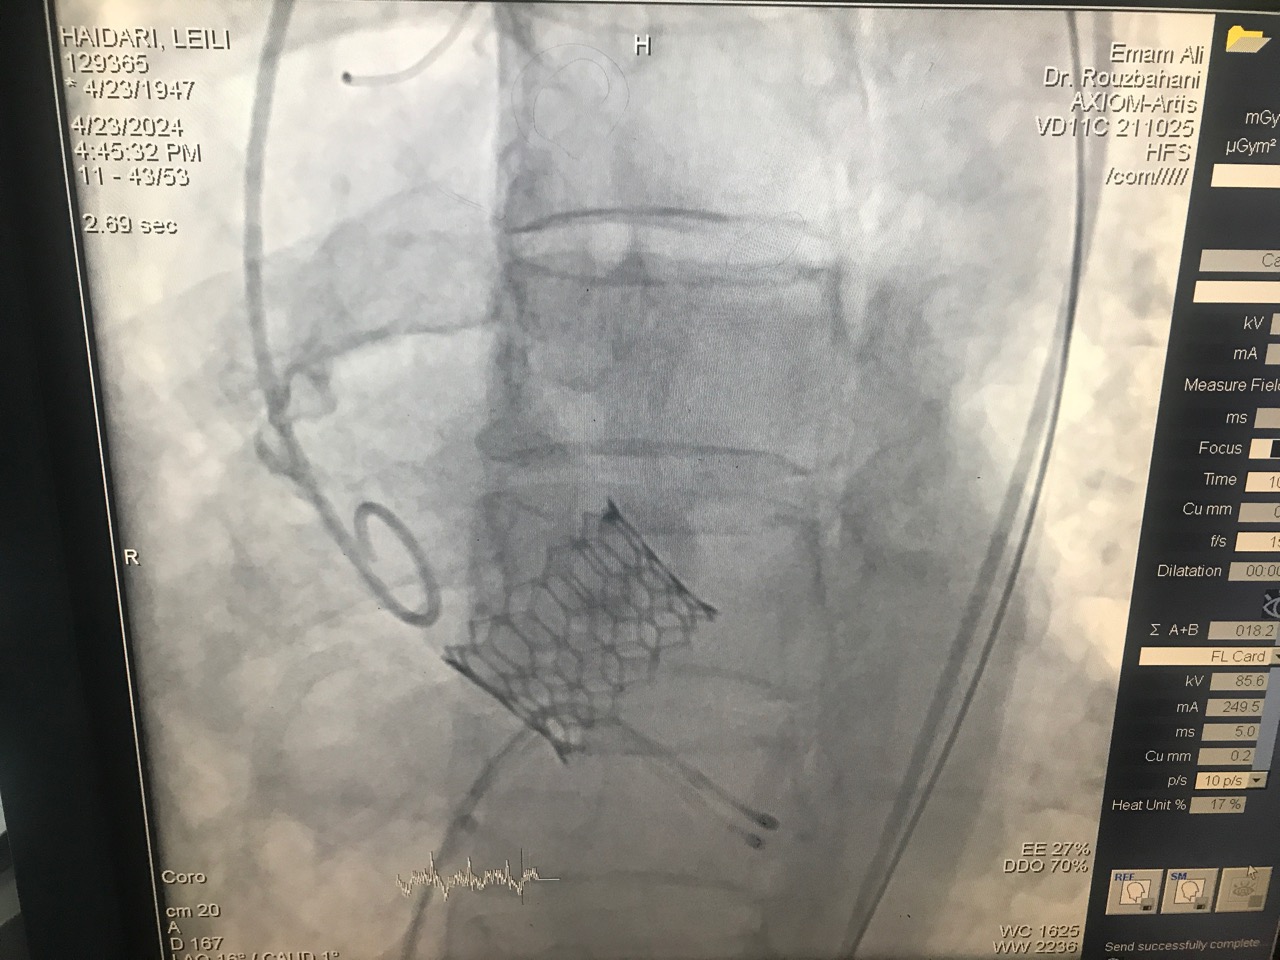

در ادامه دکتر محمد روزبهانی فلوشیپ فوق تخصص آنژیوپلاستی وآنژیوگرافی و مدیر گروه قلب و عضو هیأت علمی دانشگاه علومپزشکی کرمانشاه و عضوی از تیم عمل، نیز در خصوص عمل تاوی انجام گرفته در بخش آنژیوگرافی قلب بیمارستان امام علی(ع) کرمانشاه نیز اظهار کرد: در این عمل متخصصان با وارد کردن کتتر یا همان فنر، از راه شریان فمورال (ران) وارد شریان آئورت قلب شده و دریچه جدید را در محل مناسب قرار می دهند که این مسئله باعث میشود فرایند ریکاوری و بهبود بیمار هم سریعتر اتفاق بیفتد.

به گفته دکتر روزبهانی ، پیش از این برای تعویض دریچه آئورت، جراحان به روش جراحی قلب باز به دریچه آئورت دسترسی پیدا می کردند و دریچه معیوب تعویض می شد اما از طریق این روش، دریچه با دقت بیشتر در جای مناسب تعبیه خواهد شد و اکنون این مهم نخستین بار است که در بیمارستان امام علی (ع) و در غرب کشور انجام می شود.